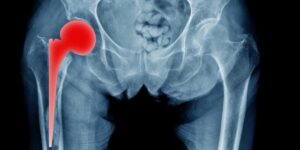

Del 2 al 6 de junio se realizaron 26 intervenciones, adicionales a las cirugías programadas de manera cotidiana. Esto ha permitido disminuir retrasos y mejorar los tiempos de espera, como parte de la Estrategia “Cero Rezago”.

Así, el Hospital General (HG) Tampico, en Tamaulipas, realizó 26 cirugías de reemplazo total de rodilla y cadera en beneficio de derechohabientes de entre 55 y 89 años, con el fin de mejorar su calidad de vida.

De acuerdo con el jefe del servicio de Traumatología y Ortopedia, Juan Manuel Castillo Rivera, las y los pacientes intervenidos padecían afecciones crónicas que les causaban malestar grave:

“Los pacientes presentaban sintomatología severa que incluía dolor crónico intenso, limitación funcional importante para la movilidad, deformidades estructurales en las articulaciones de la rodilla, y dependencia prolongada de analgésicos”.

Agregó que las y los derechohabientes atendidos fueron dados de alta 48 horas después de haberse sometido a cirugía. A la fecha reciben apoyo por parte del personal del servicio de Terapia Física y Rehabilitación del hospital, para ayudarles a recuperar, en un plazo de seis a ocho semanas, su movilidad y autonomía:

“Estas intervenciones impactan directamente en la calidad de vida de los pacientes, al restituir su capacidad para movilizarse con mayor seguridad y autonomía. Además, al disminuir el dolor y la limitación funcional, se reduce de forma importante el riesgo de caídas y fracturas”.